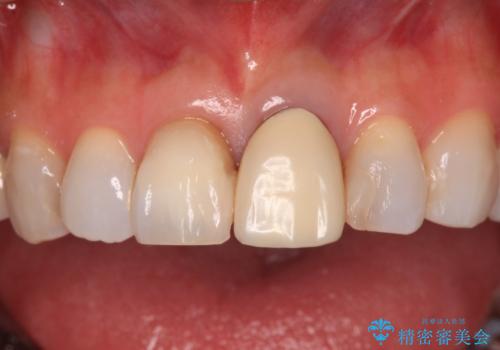

- 変色した保険の前歯のクラウンを交換したいとのことで来院された患者様です。

中心左側の歯はクラウンが装着されており、右側は神経組織が除去されて多少変色している状態でした。

右側の歯も将来的にもっと変色する可能性があるため、前歯2本をオールセラミッククラウンにて補綴治療を行うこととしました。